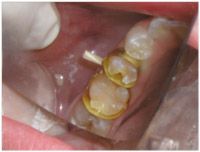

Fig. 1: T-bands with wooden wedge (Note: Isolite mouthprop is used.)

T-bands

The T-bands come in a variety of materials and thicknesses, and widths. The 0.001” brass matrix is available in narrow, wide, curved and straight forms. I suggest the 0.001” straight narrow brass matrix for cuspids (Class III restorations), primary molars, and bicuspids; the wide matrix for permanent molars (Fig. 1).

The advantages of T-bands is the cost of the disposable band and the ease of use. The disadvantage of T-bands is the difficulty in getting excellent contours and contacts.